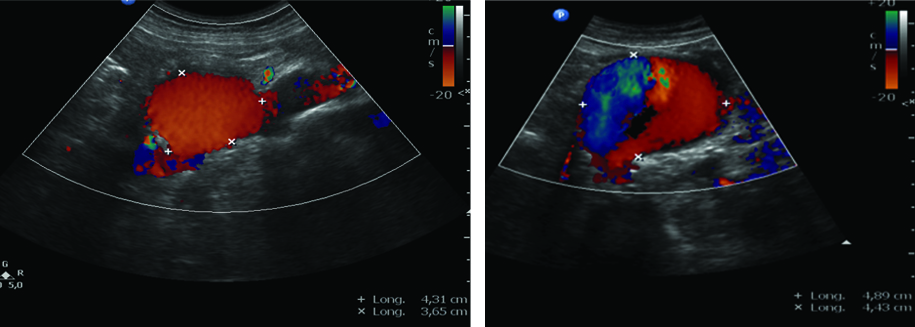

La Ecografía es el método de elección para el diagnóstico inicial, no solo por su amplia disponibilidad sino porque permite rápidamente la realización de mediciones en el plano longitudinal, anteroposterior y transverso (Fig. 26). Está indicada para la realización del screening del aneurisma de aorta abdominal en pacientes mayores de 65 años y con factores de riesgo.

La técnica de evaluación del aneurisma de aorta abdominal incluye mediciones, las cuales deben realizarse desde los bordes externos de la misma. En el plano longitudinal se examina la aorta desde el diafragma hasta la bifurcación ilíaca, y se miden el diámetro anteroposterior y la longitud del aneurisma. En el plano axial se mide el diámetro transverso. Para categorizar el tipo de aneurisma se examina la relación y distancia del aneurisma con respecto a la emergencia de la arteria mesentérica superior, de las renales y de la bifurcación ilíaca. Se examinan las arterias ilíacas y se mide su diámetro para determinar si están comprometidas. Las arterias ilíacas primitivas tienen un diámetro anteroposterior normal de hasta 11 mm (Fig 27).

El DC permite una evaluación más exhaustiva, con la cual no solo podemos determinar con precisión los límites de la dilatación aneurismática sino que también hace posible percibir la turbulencia en el flujo dentro de la misma (Fig. 28).

Al realizar la evaluación ecográfica, el especialista no debe dejar pasar por alto la presencia de trombosis mural o trombos de flotación libre en su informe, lo cual en una segunda etapa estará íntimamente relacionado con el abordaje terapéutico del paciente (Fig. 29).

Los controles imagenológicos post tratamiento son de importancia, y es indispensable la caracterización morfológica del aneurisma y la endoprótesis. De esta manera, debemos medir el tamaño del aneurisma, la presencia de flujo dentro de la prótesis, la ausencia de flujo peri protésico, la presencia de flujo en arterias renales y la adecuada velocidad de flujo en las arterias ilíacas (Fig. 41, 42 y 43).